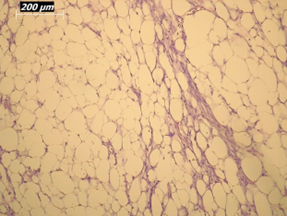

Renal artery embolization was performed under local anesthesia using the Seldinger technique, with complete occlusion confirmed angiographically (Figures 3-4). Six days later, a transabdominal left radical nephrectomy was performed. Intraoperatively, the kidney appeared markedly enlarged and deformed, containing cystic and soft-tissue components but without invasion of adjacent structures (Figures 5-6). The operation was uneventful, with minimal blood loss (approximately 300 mL) and no transfusion requirement. The postoperative course was smooth, and the patient was discharged on postoperative day five in good condition. Histopathological examination revealed that the upper pole lesion corresponded to a low-grade clear cell RCC with focal necrosis (Figures 7-8). The larger lesion was identified as a well-differentiated liposarcoma (Figures 9-10), correcting the initial radiologic misdiagnosis of angiomyolipoma. At the three-month follow-up, the patient remained asymptomatic. Laboratory results indicated mild renal impairment (creatinine 169 µmol/L, urea 9.2 mmol/L) but normal inflammatory markers. Ultrasonography revealed no recurrence or lymphadenopathy. Nephrology follow-up was continued due to reduced renal function. Six months postoperatively, CT imaging of the thorax, abdomen, and pelvis demonstrated no evidence of local recurrence or distant metastasis. Given the absence of standardized surveillance protocols for synchronous RCC and WDLPS, followup was conducted in accordance with conventional RCC and retroperitoneal sarcoma guidelines.

Figure 10: Higher-magnification view (20×) of liposarcoma showing mature adipocytes and minimal atypia.